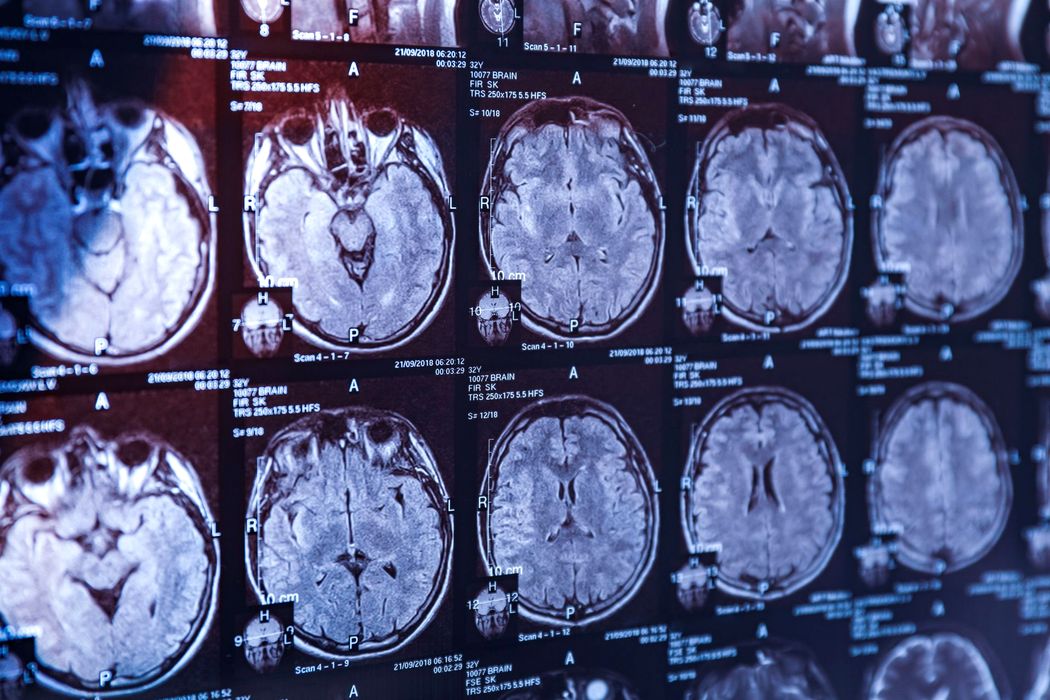

O nouă cercetare dezvăluie legătura dintre stres și dependență

O nouă cercetare dezvăluie legătura dintre stres și dependență. Momentele de stres îi împing adesea pe oameni spre obiceiuri precum consumul de alcool. Un studiu realizat la Universitatea Texas A&M (SUA) oferă o explicație clară: […]